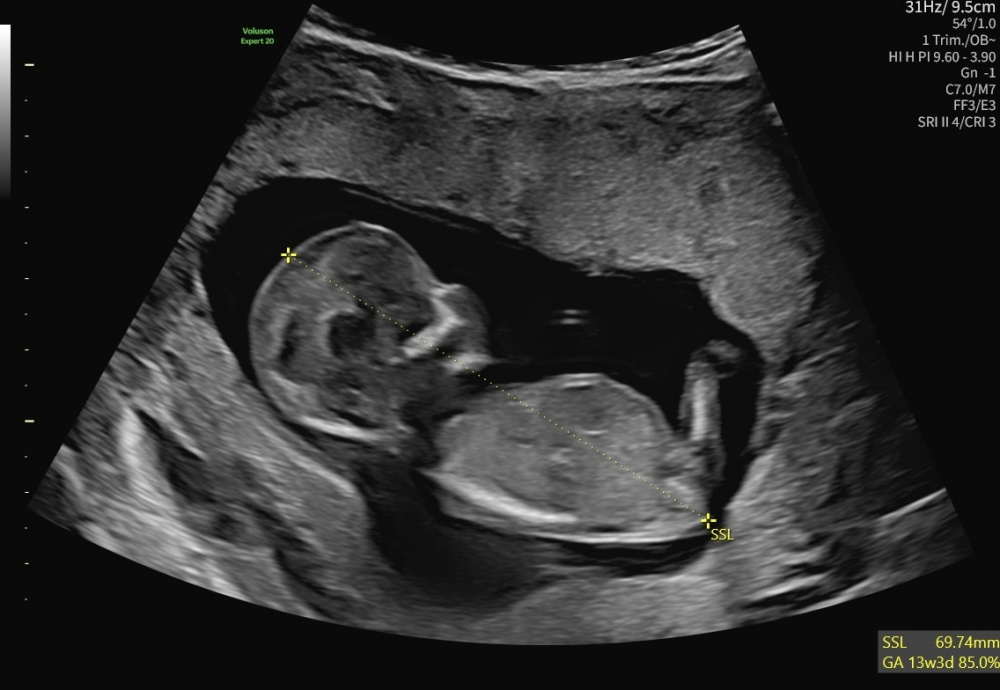

Hallo Zusammen. Das sind meine Bilder von der SSW13. Was denkt ihr?